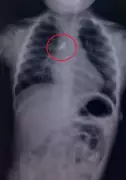

A 76-year-old woman with severe mitral regurgitation was successfully treated using India's first indigenous mitral clip device, MyClip, at a hospital in Patna, avoiding high-risk open-heart surgery.